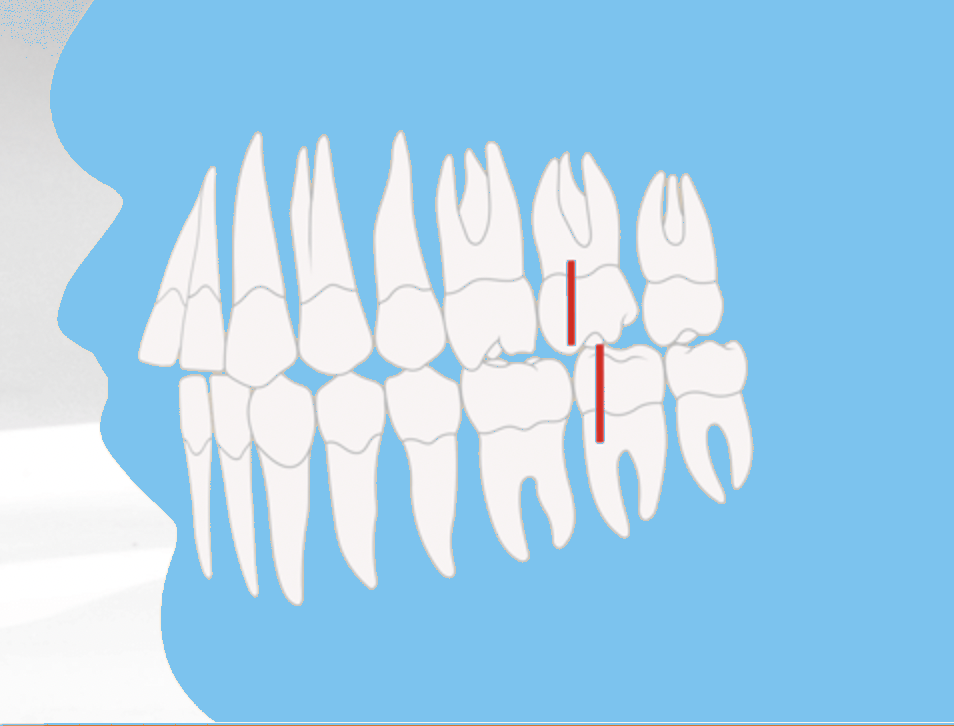

Angle-Klasse II: Überbiss (Distalbiss)

Die Angle-Klasse II beschreibt einen Überbiss bzw. Distalbiss. In diesem Fall beißt der vordere Höcker des ersten großen Backenzahns im Oberkiefer vor den entsprechenden Backenzahn im Unterkiefer. Dadurch verschiebt sich der Zusammenbiss zu weit nach hinten, was funktionelle und ästhetische Probleme verursachen kann.

Je nach Stellung der oberen Schneidezähne unterscheidet man zwischen Angle-Klasse II/1 und Angle-Klasse II/2.

- Angle-Klasse II (Distalbiss): Oberkiefer steht vor oder Unterkiefer ist zu klein. Häufig verbunden mit Überbiss oder Tiefbiss.

Angle-Klasse II/1: Nach außen gekippte Schneidezähne

Bei der Angle-Klasse II/1 sind die oberen Schneidezähne deutlich nach außen geneigt. Diese Fehlstellung führt häufig zu Schwierigkeiten beim Abbeißen und beeinträchtigt zusätzlich das Gesichtsprofil. Durch die nach vorne stehenden Schneidezähne wirken die Zähne optisch oft größer – im Volksmund auch als “Hasenzähne” bezeichnet.

Angle-Klasse II/2: Nach innen gekippte Schneidezähne

Die Angle-Klasse II/2 beschreibt ebenfalls einen Distalbiss, unterscheidet sich jedoch in der Stellung der Schneidezähne. Im Gegensatz zur Angle-Klasse II/1 sind die oberen Schneidezähne hier nach innen gekippt.

Diese Form der Fehlstellung wirkt sich sowohl auf die Zahnfunktion als auch auf die Gesichtsästhetik aus. Besonders auffällig ist, dass das Kinn im Verhältnis zum Oberkiefer zurückliegt, wodurch das Gesichtsprofil disharmonisch erscheint.

Angle-Klasse II/2: Distalbiss mit charakteristisch zurückgeneigten Frontzähnen

Angle-Klasse II

Überbiss / Distalbiss Oberkiefer zu weit vorne Unterkiefer zurück